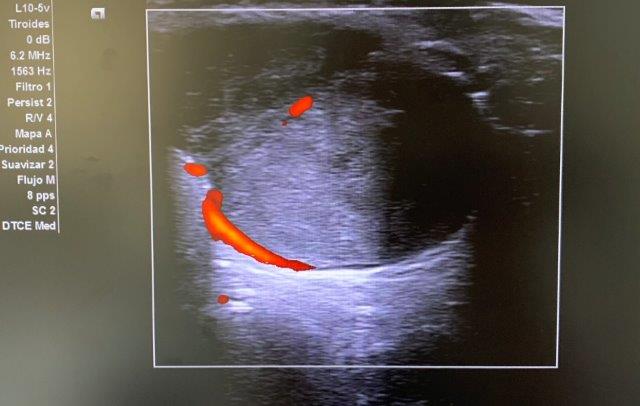

ECO POCUS: imagen isoecoica, heterogénea, redondeada con captación periférica de Doppler, que mide 26.9 x 21.7 mm (corte transversal) y 30.3 mm (corte longitudinal). Vemos un bultoma originado en la cola de glándula parótida.

Ante los hallazgos ecográficos y la persistencia del bultoma, orientamos juicio clínico hacia posible tumoración originada en parótida, con características mixtas de benignidad-malignidad (clínica + ecografía).